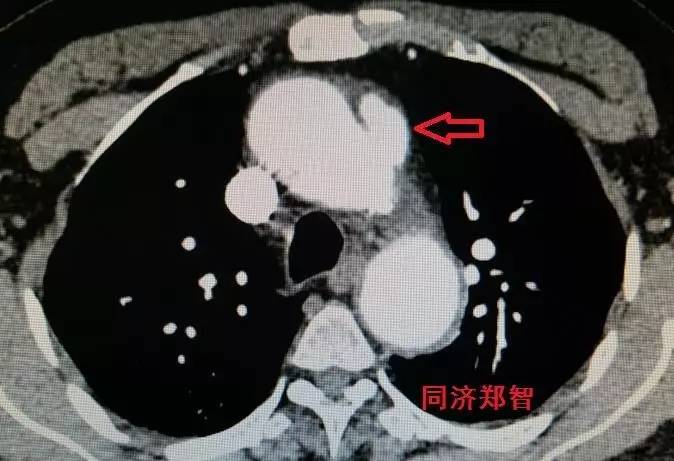

有时候平扫CT也能从血管内密度影的不同来诊断主动脉壁间血肿(图3)。平扫CT提示右肺动脉层面的升主动脉外侧为新月状稍亮的影(红箭头所示)。

图3